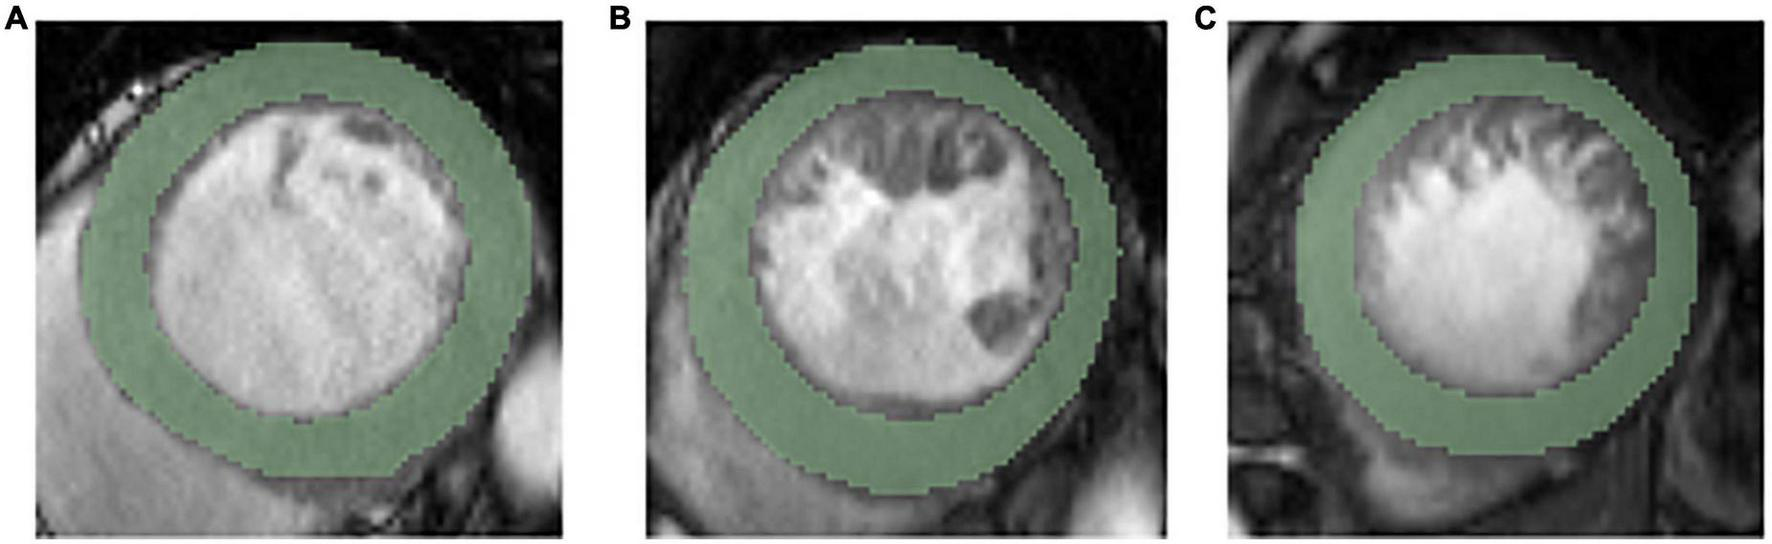

The cine images in DICOM format from selected patients were segmented using “Radiomics” (Syngo. via Frontier, Vision 1.0.0, Siemens, Germany), a dedicated prototype software, and this program employs an embedded 3D-printing technique in a semiautomatic manner to label the preoperative soft tissue. The overall procedures of this analysis scheme were composed of two major steps: first, segmentation was conducted manually; and thereafter, texture features were calculated automatically. The manual segmentation was performed independently by a chest radiologist. The region of interest was depicted around the border of each level. After segmenting a three-dimensional volume of interest (3D-VOI), texture features were automatically calculated and extracted. Additionally, all cine images were segmented by two chest radiologists (with 6 and 12 years of experience with chest CT, respectively) working together. We completely outlined the left ventricular endocardial and epicardium at basal, middle, and apical levels and excluded the papillary muscles (Figure 2).

FIGURE 2

Representative ROIs segmentation in basal level (A), middle level (B), and apical level (C).